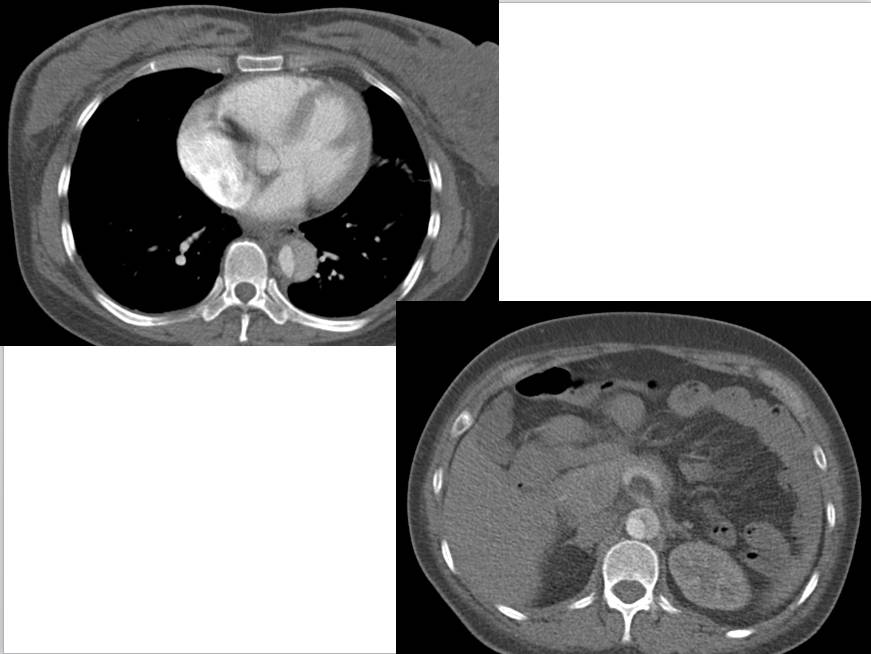

CT表现:自主动脉根部起至腹主动脉肾动脉水平可见撕裂之动脉内膜瓣影,子宫腔内可见胎儿影。

诊断结果:妊娠合并主动脉夹层(I型)。

CT平扫:内膜瓣钙化内移常可提示诊断,内膜钙化从主动脉壁外缘内移5mm以上具有诊断价值。可见主动脉局限性及广泛性增宽,或伴发有心包积液、胸腔积液等。

1、撕裂的内膜瓣:多表现为弯曲的线样低密度影,部分患者可见多个破口,内膜漂浮在管腔中。

2、破口的显示:表现为真腔和假腔之间沟通的管道,薄层的横断图像,,多平面重组技术有助于破口的显示,有时因血栓的形成或撕裂情况复杂显示困难。

3、真、假腔的显示:真假腔可同时显影,或假腔强化和排空比真腔延迟;假腔内常有血栓形成可呈略高密度影,当多个破口存在时,真假腔较难区分。一般情况下假腔较大,真腔较小。

5、主动脉夹层渗漏或破裂:Ⅰ、Ⅱ型夹层常破入心包,呈心包积液表现,积液密度较高。破入胸腔,出现单或双侧胸腔积液。破入纵隔或腹膜后,出现纵隔或腹膜后出血征像。部分夹层假腔外穿形成假性动脉瘤,以弓部多见。